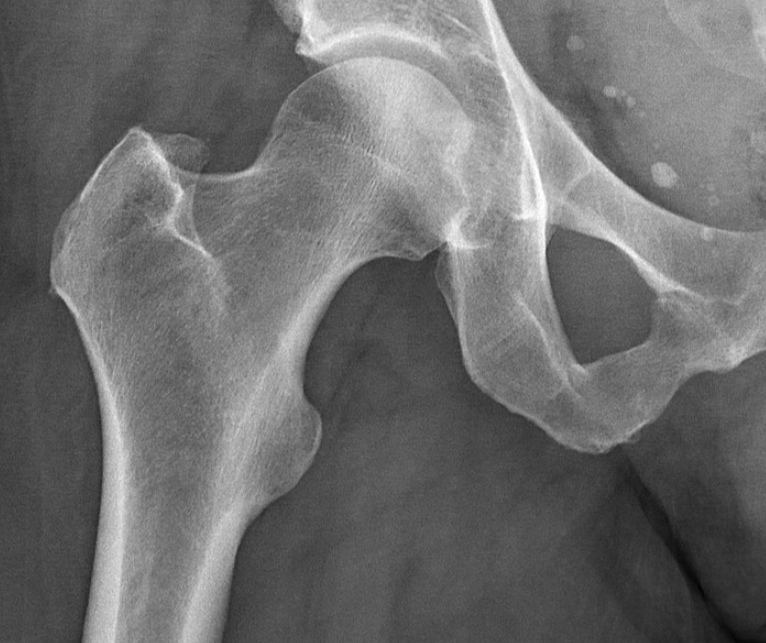

골다공증은

뼈의 골밀도가 낮아져 뼈에 구멍이 많은 증상을 말합니다.

뼈의 양이 감소하고

질적인 변화로 인해 뼈의 강도가 약해져서 쉽게 부서지거나

골절이 일어날 가능성이 높은 상태를 말합니다.